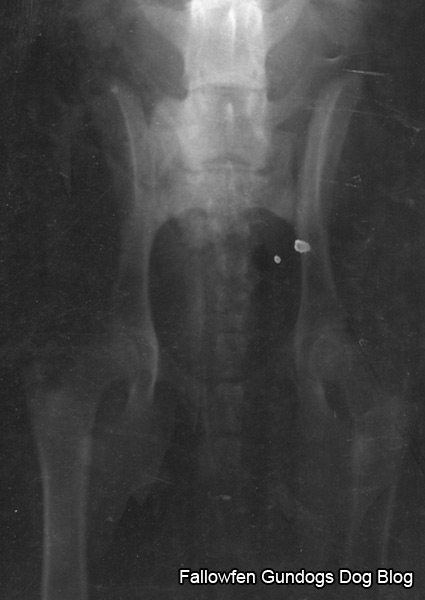

Hip scoring.

Monday, May 26th, 2008Hip scoring is a procedure used to determine the degree of hip dyplasia in dogs.The hip score is the sum of the points awarded for each of nine radiographic tures of both hip joints.The British Veterinary Association uses the following criteria to determine hip score:

- Norberg Angle

- Subluxation

- Cranial Acetabular Edge

- Dorsal Acetabular Edge

- Cranial Effective Acetabular Rim

- Acetabular Fossa

- Caudal Acetabular Edge

- Femoral Head \ Neck Exostosis

- Femoral Head Recontouring

The lower the score, the less the degree of dysplasia present. The minimum (best) score for each hip is zero and the maximum (worst) is 53, giving a range for the total of 0 to 106.